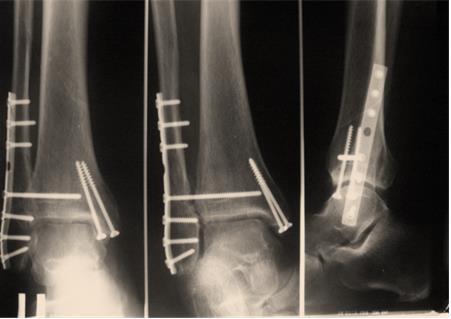

Пациент С. 64 лет, страдающий диабетом II типа, тяжелое течение. Закрытый перелом наружной внутренней лодыжек. Малоинвазивный остеосинтез лодыжек.

Рисунок 3Рисунок 4Рисунок 5(а)Рисунок 5(б)Рисунок 6 (а,б) Результат через 6 недель после операции.